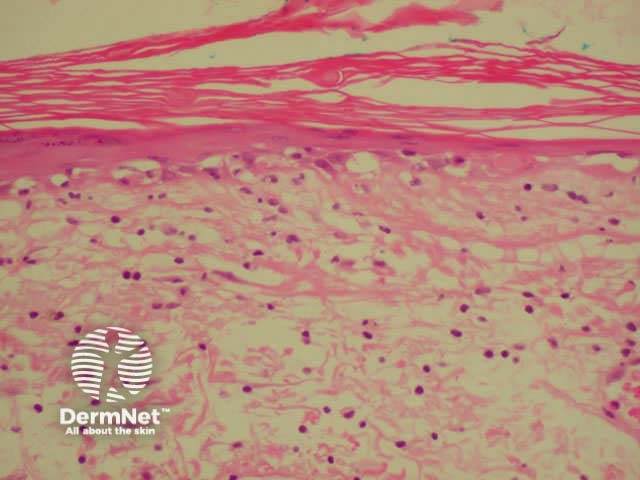

Dermatopathological findings in SLE include a lichenoid tissue reaction and a band of immunoglobulins at the dermo-epidermal junction (detected by direct immunofluorescence of clinically involved skin).

Dermatopathology of systemic lupus erythematosus This shows a dense perivascular and periadnexal lymphocytic inflammatory infiltrate and interface changes with vacuolar degeneration of basal layer

High-power view